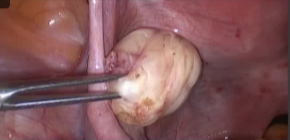

![]() |

在开始该程序之前,会先进行手动分割操作。 随后,一款专用软件会自动制定出最佳的治疗方案。

在操作过程中,会进行多次超声波治疗,直至覆盖住足够的子宫肌瘤体积。 每次超声处理持续 20 至 40 秒,每次超声处理之间会有冷却时间(最长可达 90 秒)。 磁共振成像技术中质子共振频率的偏移特性使得能够监测每一个治疗点的温度。

经过治疗后,会进行核磁增强以评估被切除区域的范围。